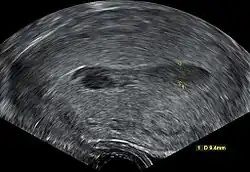

Transvaginal ultrasonography of a hematometra after childbirth, seen as a hypoechoic (darker) area within the uterine cavity. The cervix is located to the left in the image, and the fundus is located to the right. | |

Although hematometra can often be diagnosed based purely on the patient's history of amenorrhea and cyclic abdominal pain, as well as a palpable pelvic mass on examination, the diagnosis can be confirmed by ultrasound, which will show blood pooled in the uterus and an enlargement of the uterine cavity.[5][6] A pyelogram or laparoscopy may assist in diagnosing any congenital disorder that is suspected to be the underlying cause of the hematometra.[3]